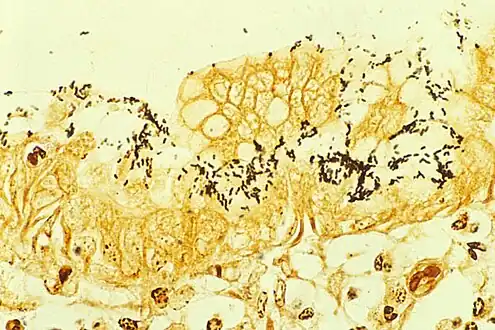

Helicobacter pylori colonized on the surface of regenerative epithelium, stained with the Warthin–Starry method.

Clusters of bacteria (arrow) shown on Warthin–Starry stain.

Warthin–Starry stains organisms dark brown to black, and the background light golden brown/golden yellow.[5]